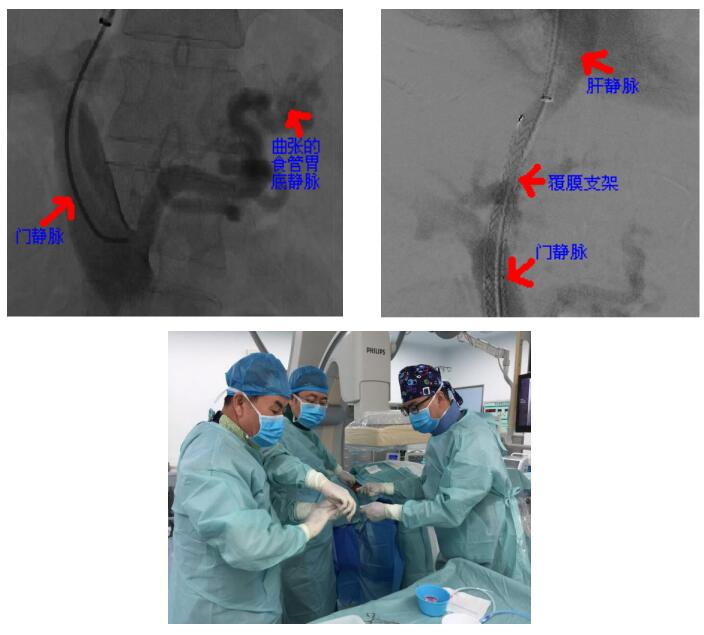

近日,乌海市人民医院介入血管外科成功自主完成经颈静脉肝内门体分流术(TIPS)一例。患者梁某某男45岁,有乙肝、肝硬化病史,此次因食管胃底静脉曲张破裂而导致大出血,在当地医院经保守治疗后患者出血没有得到有效控制,连续多日便血,每日约500ml,情况十分危险。转入我院后,我院介入血管外科在详细为其进行了诊查后,为患者实施了TIPS手术。手术成功建立门体分流通道,并栓塞了出血的食管下段胃底静脉。术后患者未再出现便血,术后第二天,患者就可以进流食,目前患者状态恢复良好。

TIPS作为一项高精尖介入手术,是具有代表性的介入四级手术,属于难度比较大的手术,手术技术要求很高,较传统的治疗方式有着微创、高效的优点,在区内处于新兴发展阶段,本例TIPS手术的成功实施,标志着乌海市人民医院介入血管外科在肝硬化上消化道出血救治这一领域里处于自治区先进水平,也标志着乌海市人民医院介入血管外科整体技术水平达到了一个新高度。该手术的成功开展,将大大降低了本地区肝硬化患者因突发消化道大出血危及生命的风险。